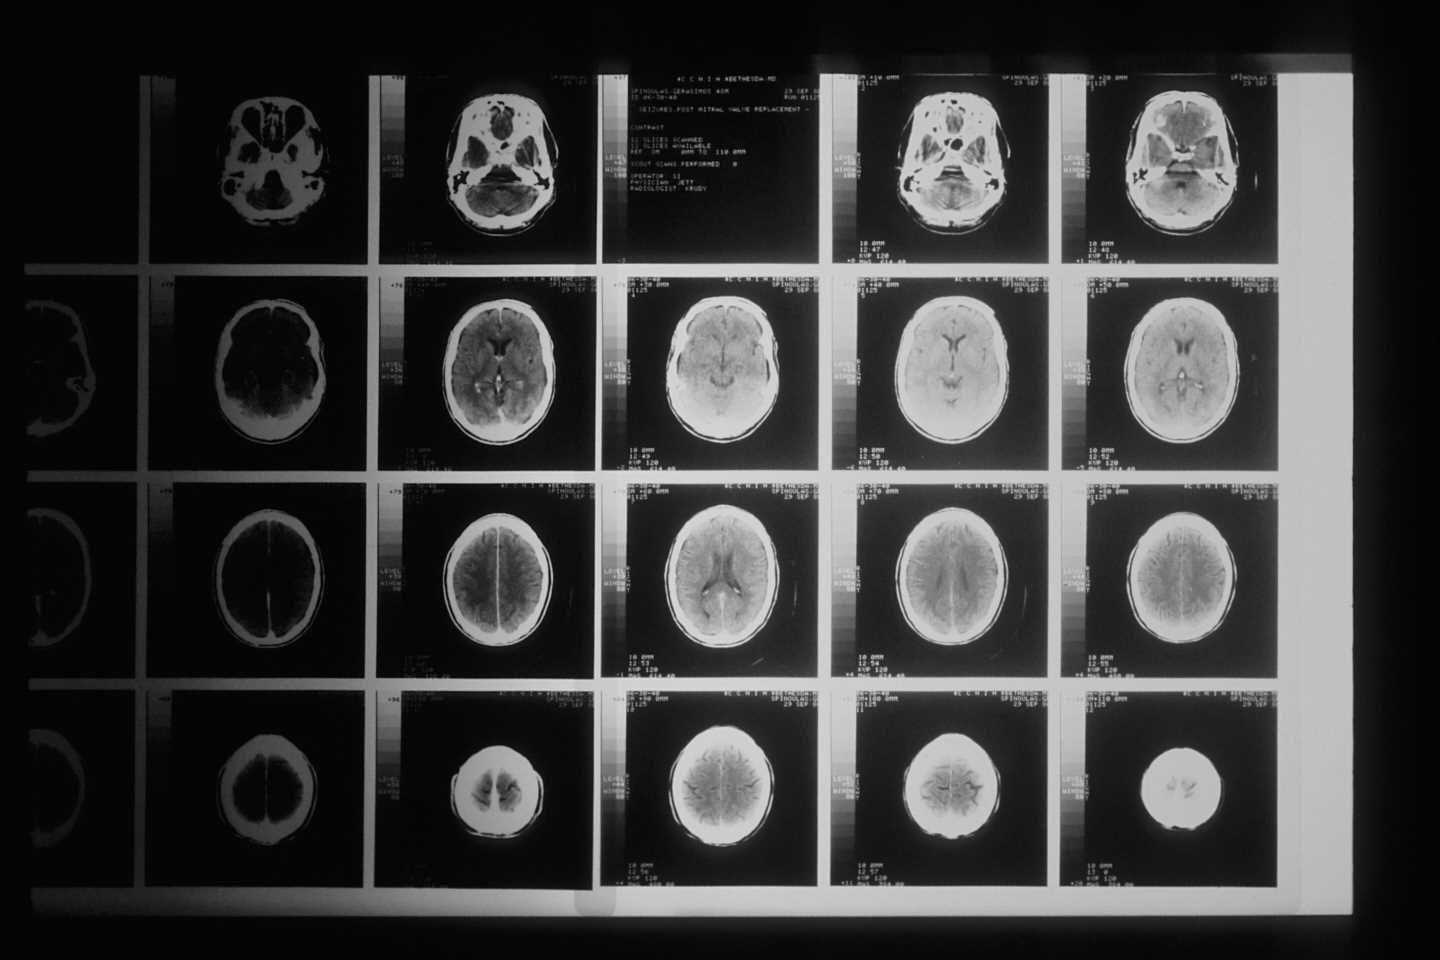

A study published in the journal Arthritis & Rheumatology characterizes for the first time the alterations in the gray matter volume in adolescents affected by juvenile fibromyalgia, and it analyzes its functional and clinical relevance. The study contributes to identifying potential risk factors that will help testing the efficiency of different treatments to reverse these brain alterations. The new research is led by the postdoctoral researcher Maria Suñol and the lecturer Marina López Solà, from the research group Pain and Emotion Neuroscience Laboratory of the Faculty of Medicine and Health Sciences and the Institute of Neurosciences (UBNeuro) of the University of Barcelona.

The study reveals that the adolescents with juvenile fibromyalgia have less gray matter in the anterior-midcingulate cortex (MCC) region, a brain region which is decisive for pain processing. This feature could be related to the excessive engagement of brain circuits that process pain and it points out to the existence of a reorganization with these neuronal circuits.

The most affected patients by the pathology—and with more symptoms—also show an increase of volume in the frontal regions of the brain that is related to the creation of narratives about oneself and the emotional processing and regulation.

This increase in volume could reflect a certain immaturity in the process of the development of frontal circuits involved with emotion and language. “These findings strengthen the need to consider therapeutic strategies aimed at modulating the activity in these circuits in order to reverse the harmful narratives patients might feel about themselves,” notes Maria Suñol, first author of the study.